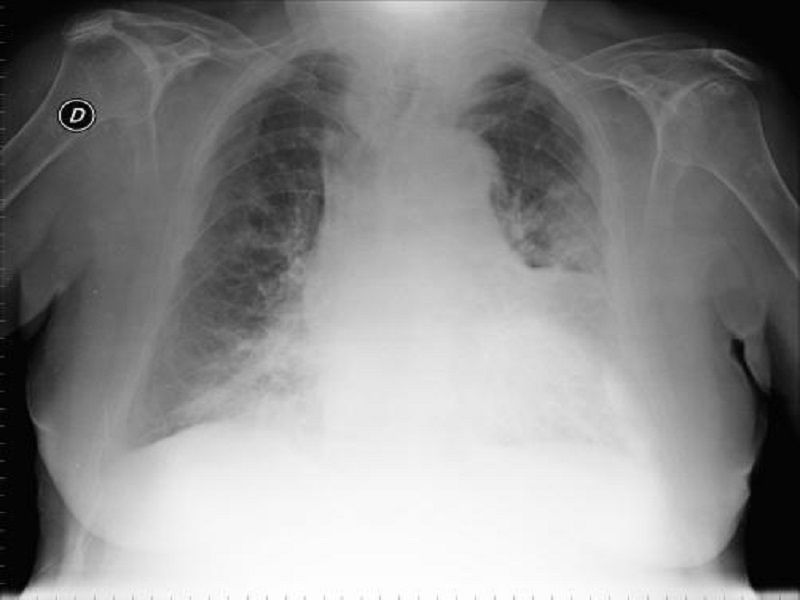

Immagina di guardare attraverso un vetro smerigliato: puoi ancora vedere la luce e le forme, ma sono offuscate, meno definite. Allo stesso modo, l'addensamento a vetro smerigliato (in inglese, Ground-Glass Opacity o GGO) è un termine usato dai radiologi per descrivere un'area nei polmoni che appare più densa del normale alla TAC, ma dove i vasi sanguigni e le strutture bronchiali rimangono ancora visibili. In pratica, l'aria negli alveoli (i piccoli sacchi d'aria nei polmoni) è parzialmente sostituita da qualcos'altro, come fluido, tessuto o cellule infiammatorie.

Importante: Un addensamento a vetro smerigliato non è una diagnosi specifica, ma piuttosto un reperto radiologico che può essere causato da diverse condizioni.